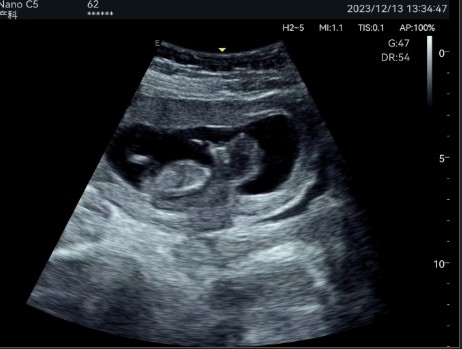

Abdominal diagnostics, obstetrics and gynecology: Allows detailed evaluation of internal organs and structures.